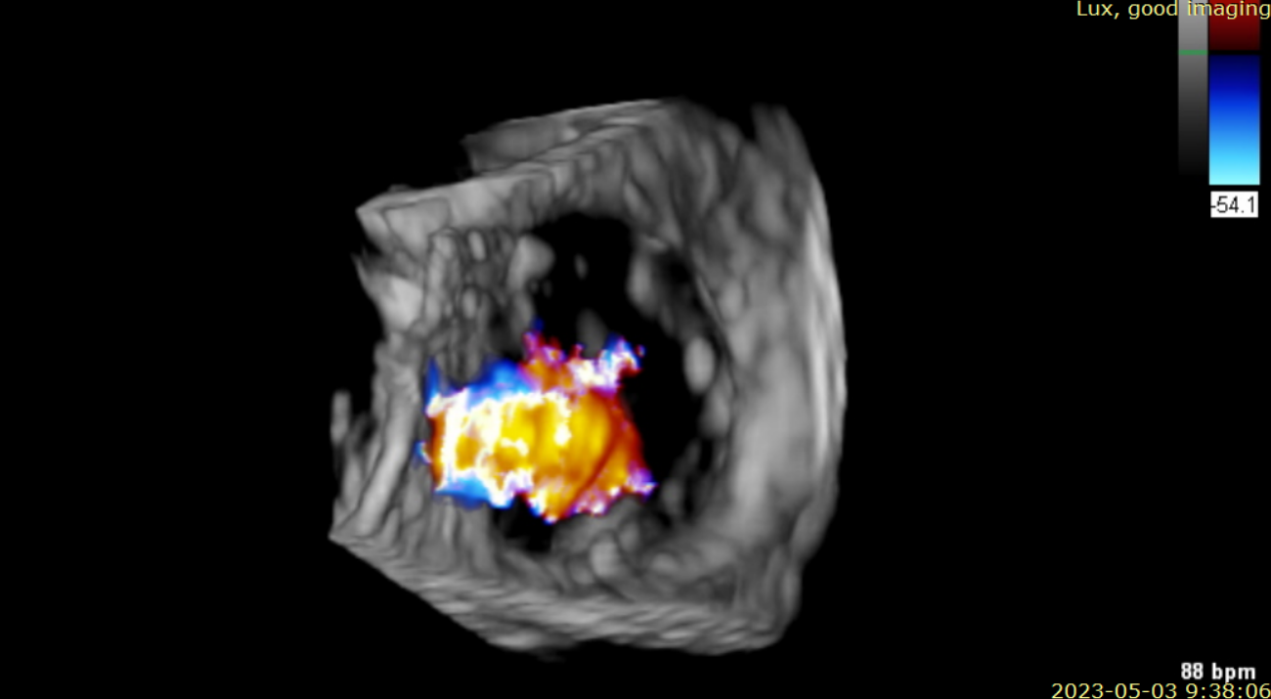

術(shù)后超聲提示無瓣周漏

術(shù)后超聲提示僅殘余輕微瓣周漏

術(shù)后Azeem Latib教授對LuX-Valve Plus經(jīng)血管三尖瓣置換系統(tǒng)的器械性能和治療效果大為稱贊,并且認為LuX-Valve Plus的手術(shù)體驗非常好。從治療效果來看,術(shù)后即刻超聲顯示三尖瓣反流幾乎完全消失,血流動力學改善顯著,患者恢復(fù)快。在面對復(fù)雜解剖結(jié)構(gòu)、超聲影像質(zhì)量不佳、有起搏導(dǎo)線干擾時,Lux-Valve Plus也體現(xiàn)了極強的適應(yīng)性。Thomas Modine教授參與了術(shù)中指導(dǎo),他同樣再次肯定了LuX-Valve Plus術(shù)中操作的便捷性,認為LuX-Valve Plus容錯率高,對術(shù)中影像的依賴小,并表達了后期希望可以更多地應(yīng)用LuX-Valve Plus三尖瓣置換系統(tǒng)于臨床實踐,讓更多的三尖瓣重度反流患者盡早獲益,改善預(yù)后。